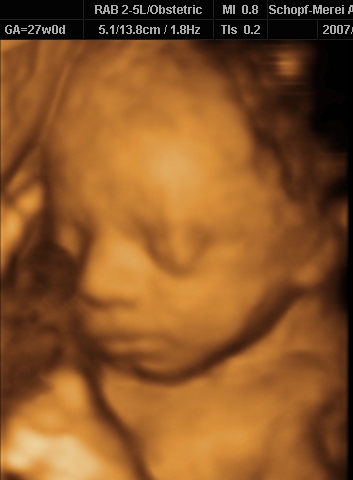

Zsófi fejecskéje (álla alatt húzódik a köldökzsinór, az bezavart a képbe)

Ugye most vagyok a 29. hét elején. Babuba 1700 (!)

gramm, a doki azt mondta, gyönyörűen fejlődik, egészséges, minden oké.

Egyébként végig aludt, 1x-2x kinyitotta a szájacskáját, meg mosolygott. Forgolódtam az oldalamra, vissza, doki bökdöste a hasamat, de őt semmi nem érdekelte. Lehet, azért van kicsit lebiggyesztett szájtartása a fotón, mert azt akarta mondani: Haggyatok má békéééén!